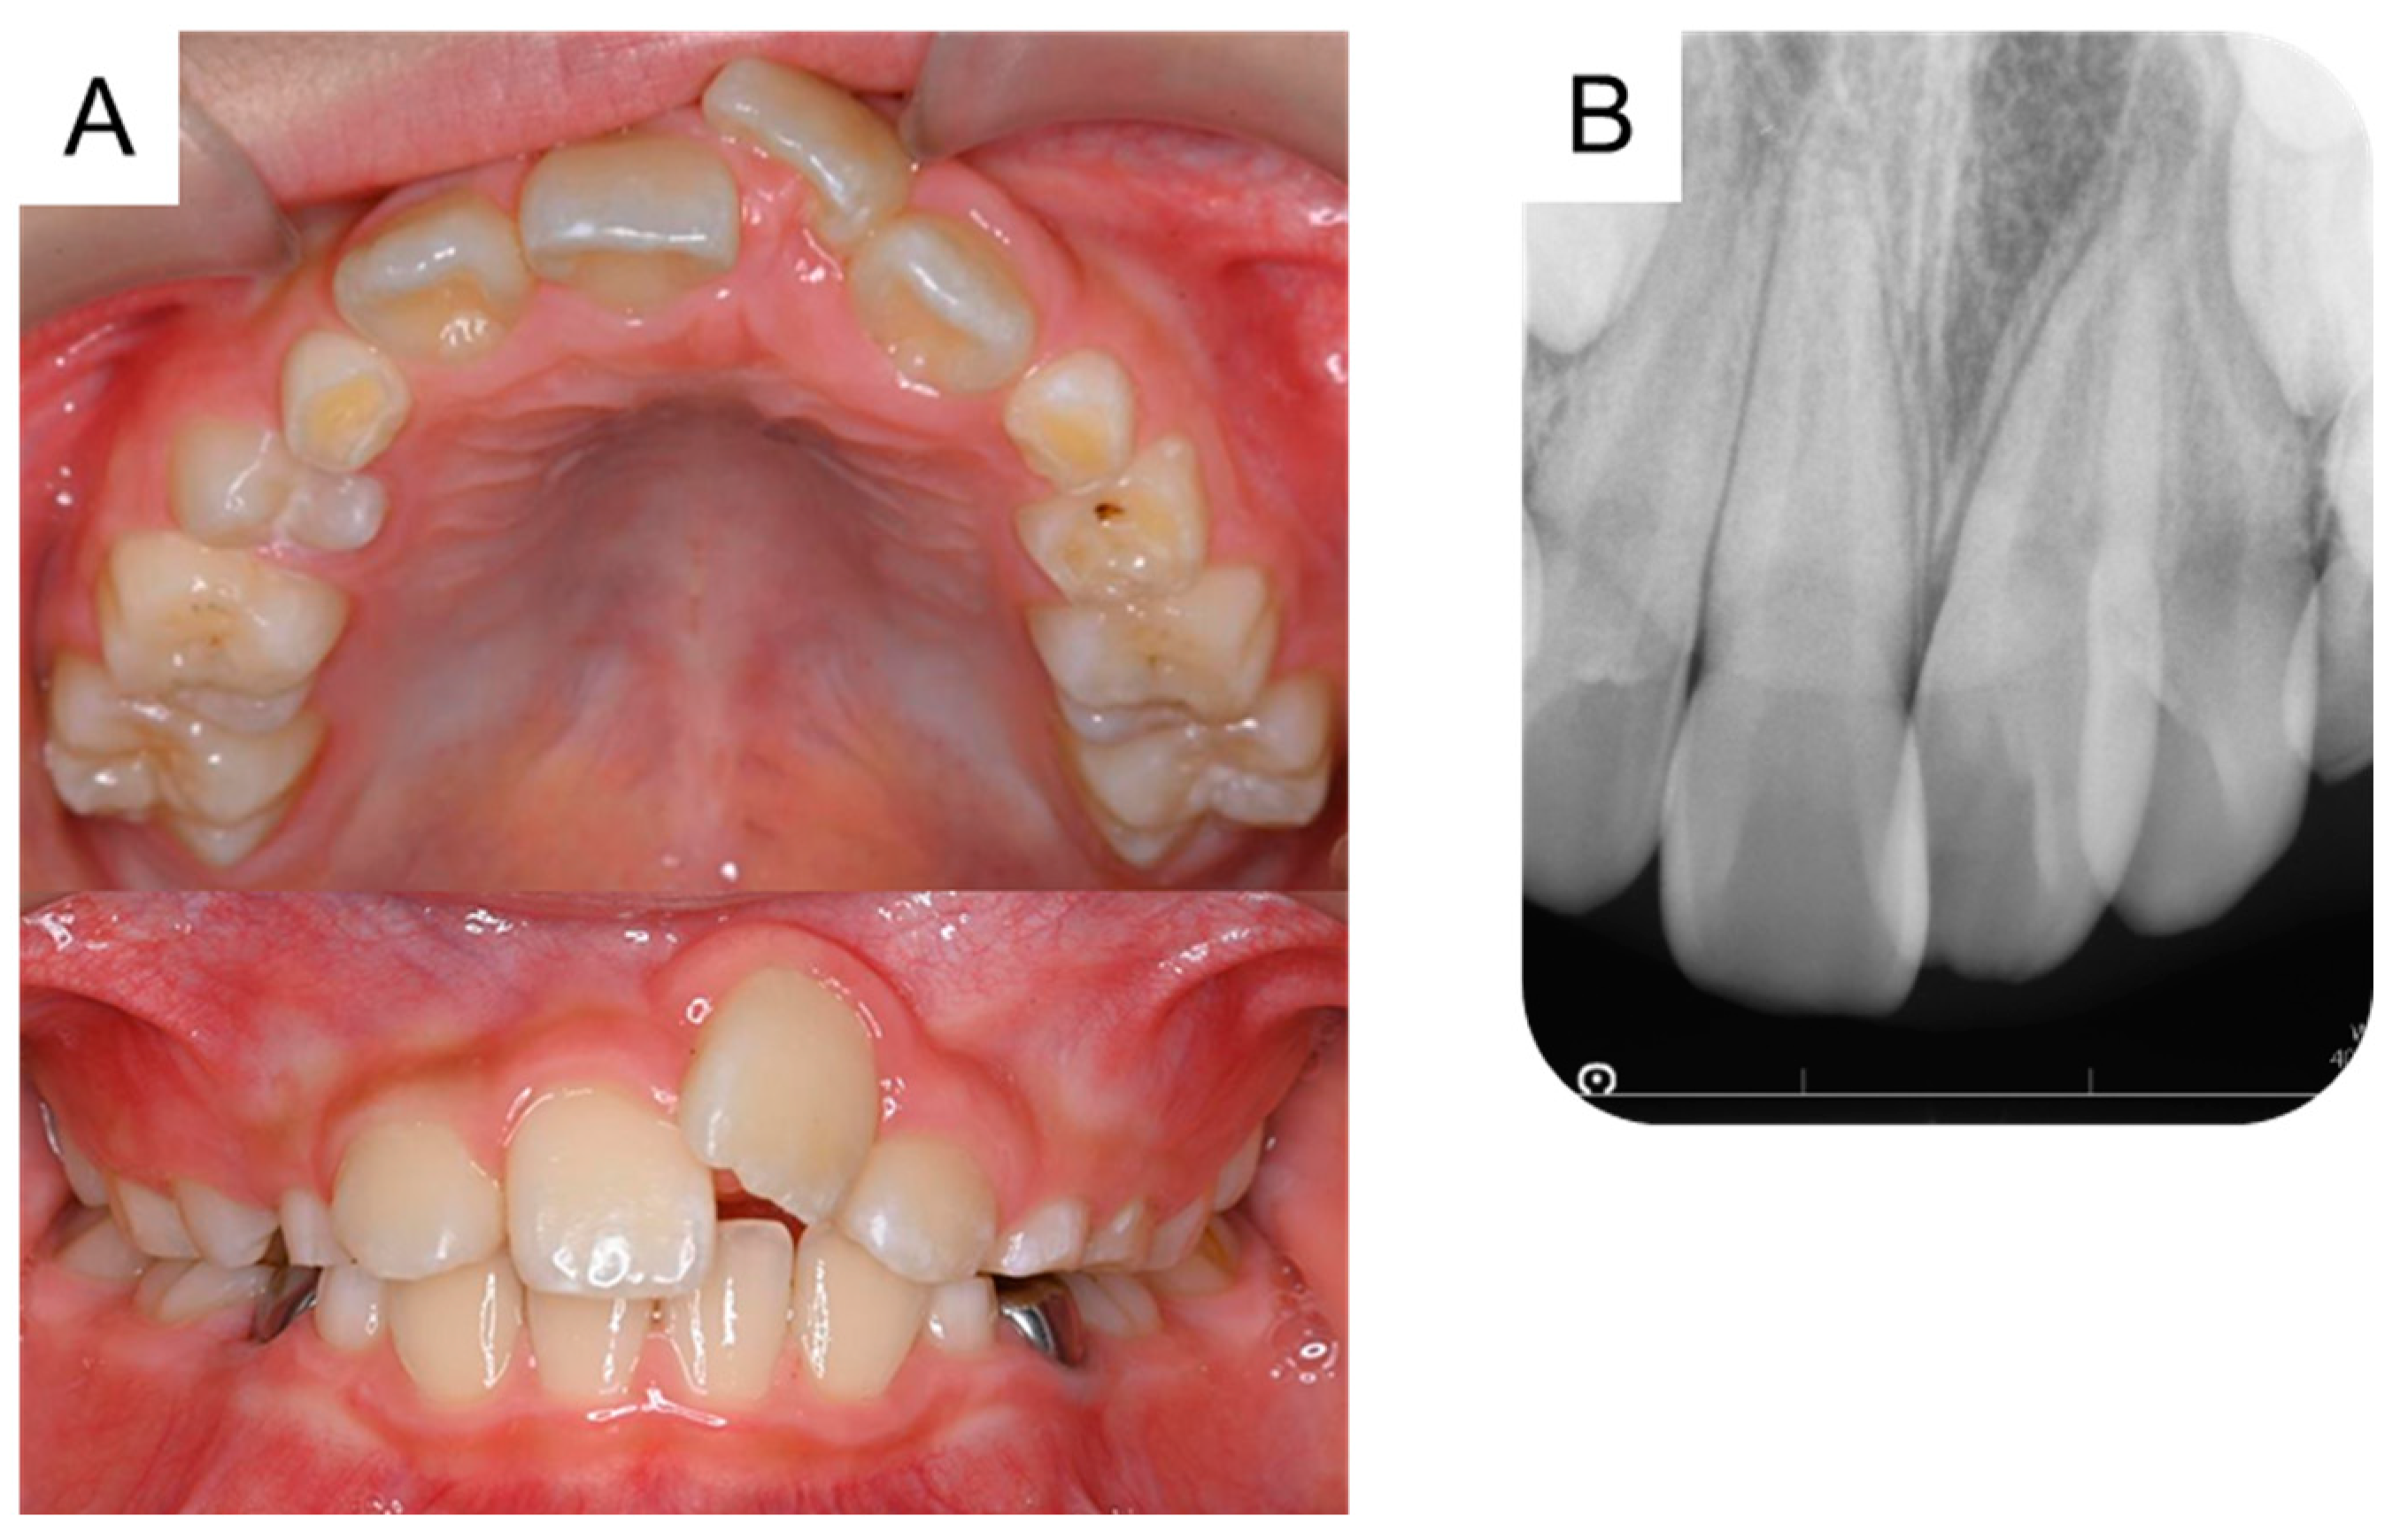

At 5 years and 5 months of age, a supplemental supernumerary tooth (first supernumerary tooth) was detected near the permanent maxillary left central incisor (Figure 1A). This supernumerary tooth gradually erupted and was extracted 6 months later (Figure 1B).

Figure 1. Extraction of the first supernumerary tooth. (A) Periapical radiograph of the first supernumerary tooth detected at the age of 5 years and 5 months. (B) Extracted first supernumerary tooth at the age of 5 years and 11 months. Scale bar: 5 mm.